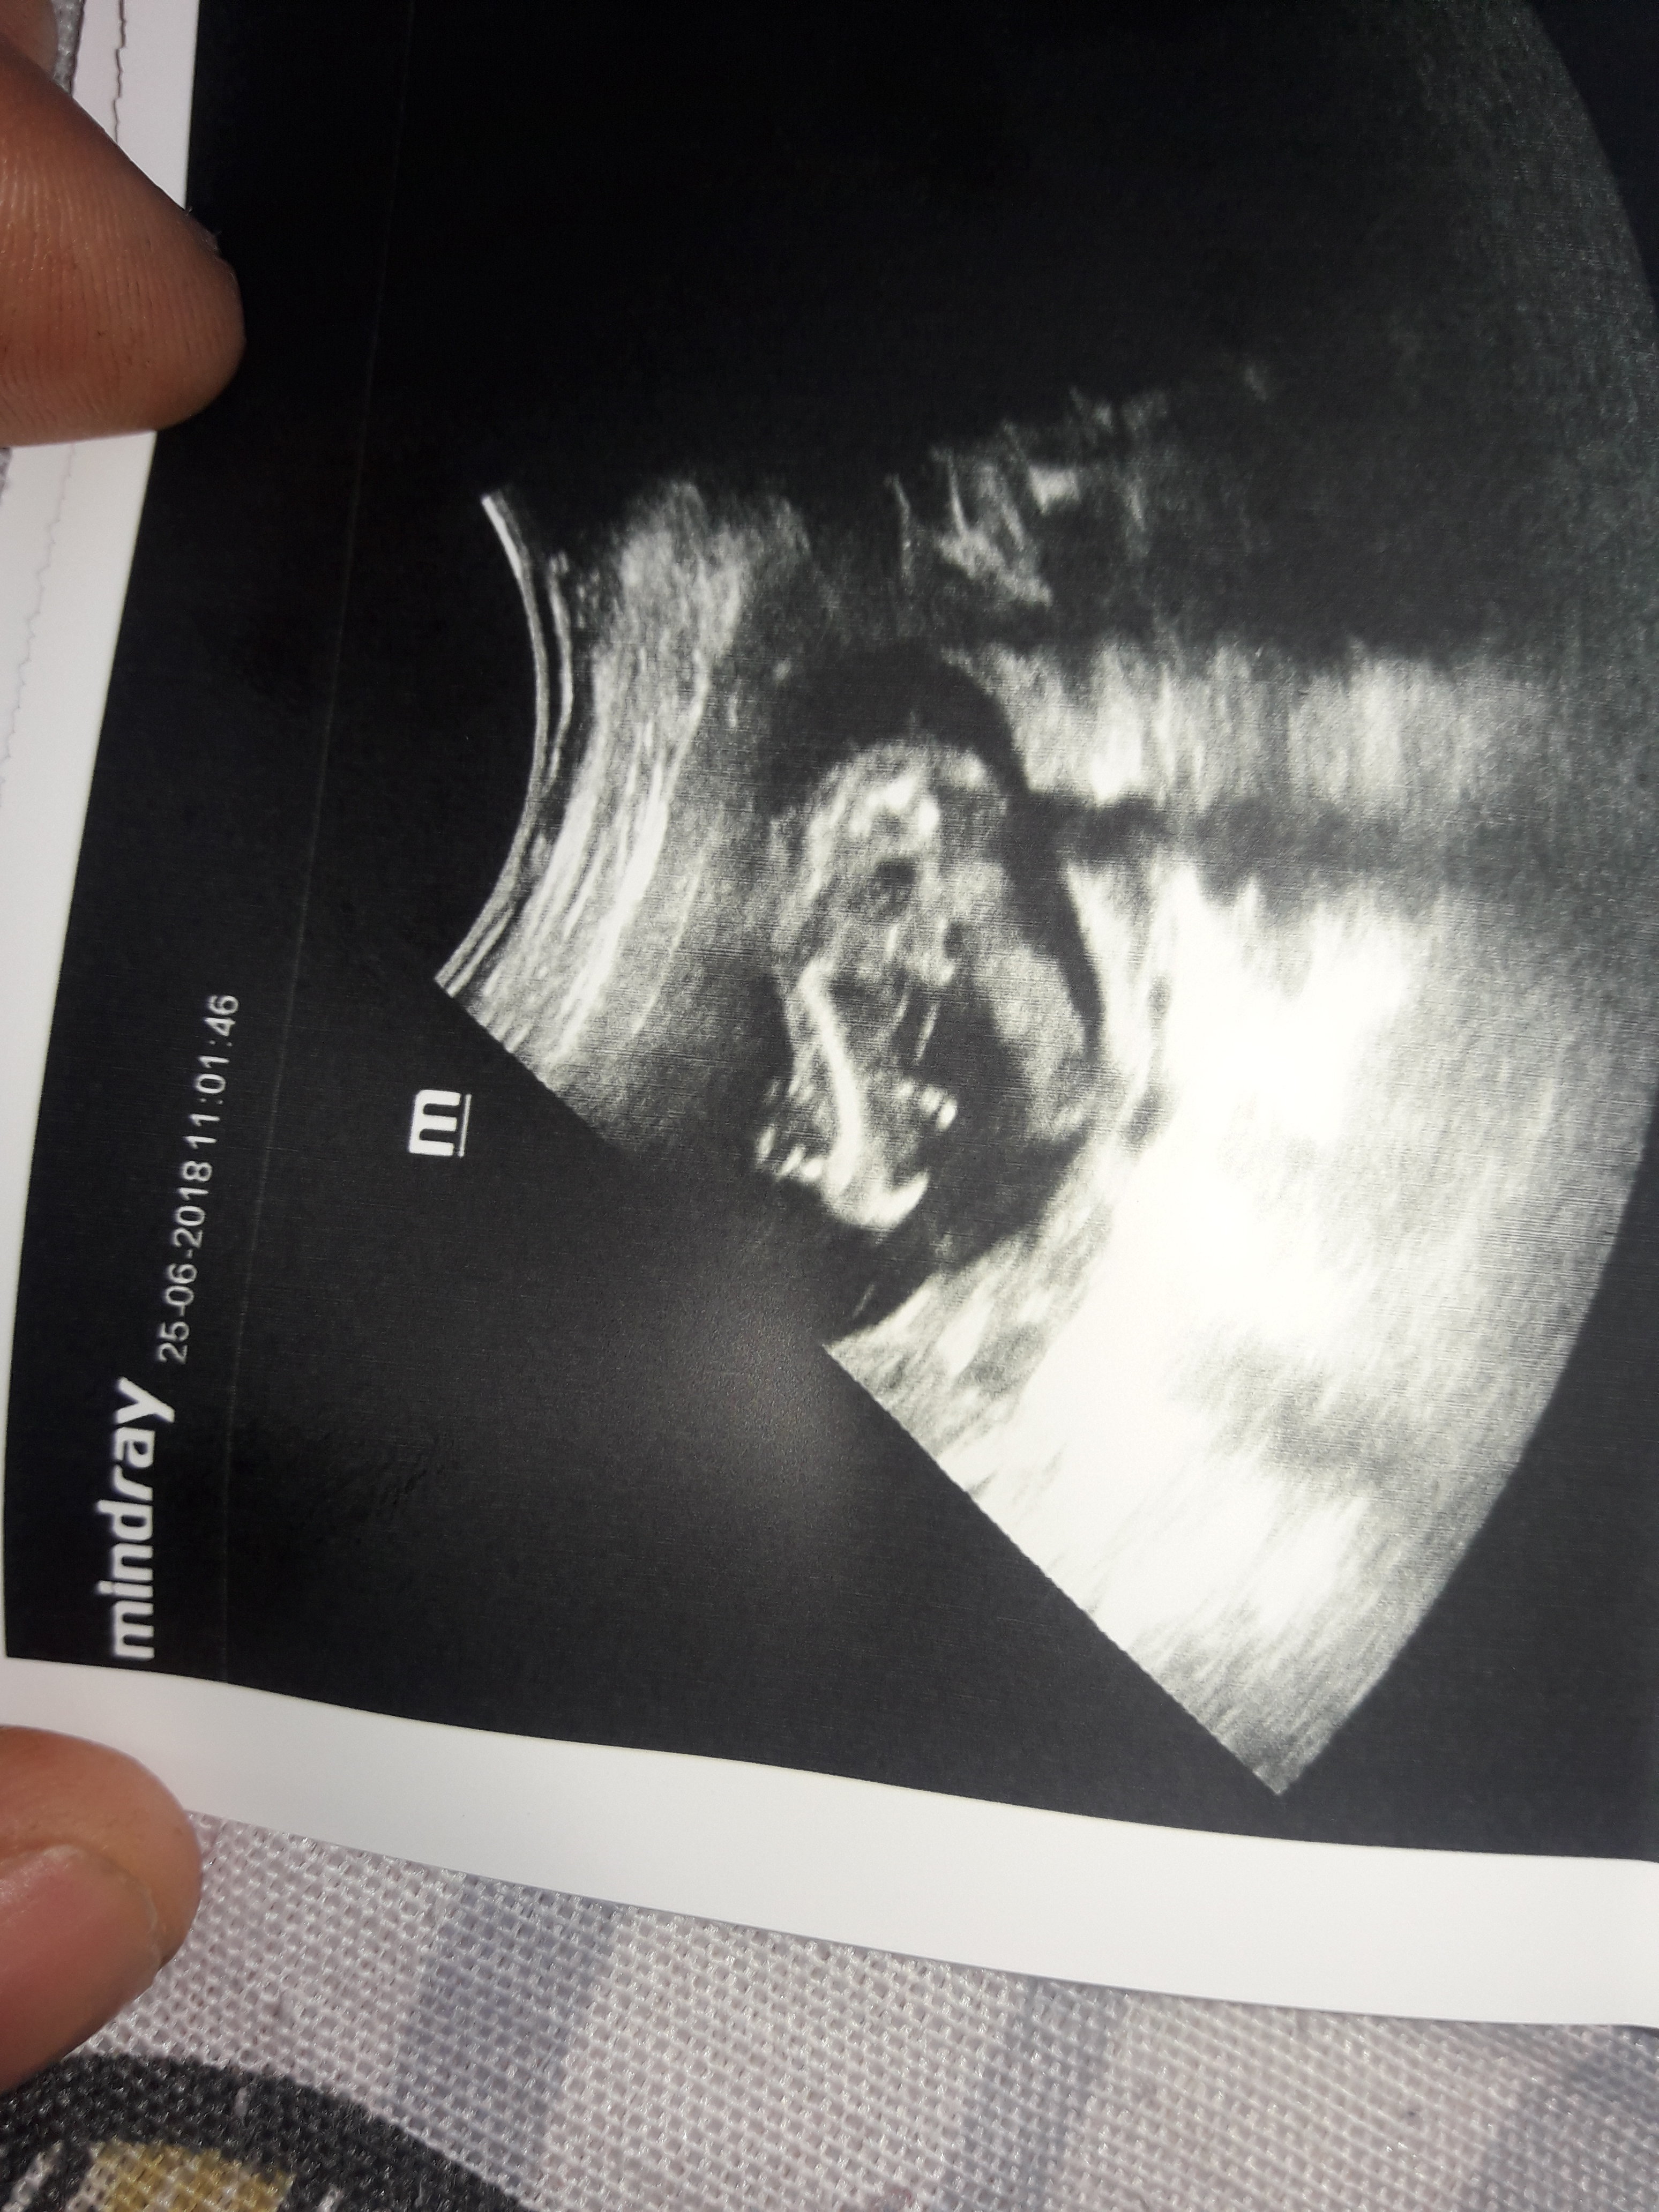

merhaba bu bebegimin 12 haftalik resmi doktor bu haftada erkek dedi suan 18 haftaligiz ve bir baska doktor 18 haftalikken ultrasonda bebek bagdas kurmus bacaklarini acmiyor kiz olabilir dedi simdi kafam karisti 12 haftalikken ki ultrason resmindeki bacak arasindaki cikinti ne anlama geliyor lutfen yorumlarmisiniz

Benimde bakarmısınız lütfen doktor erkek dedi sonra gene erkek dedi kıza benziyor dedi yok yok erkek dedi bende sasrdm

aslinda merak ettigim su okla gosterdigim yer.12 haftalik bebegin genital organlari bu haftada tam olusmus olabilir mi ve ultrasonda bu kadar net gorulebilir mi ki doktorum cok net bir sekilde erkek demisti

Bebeğin cinsiyeti oluştuğu andan itibaren bellidir aslında ama bu en erken nub teoirisi ile 12. haftada öğrenilebilir. Bu haftalarda yanılma payı yüksektir bu nedenle benzer paylaşımların hepsine bebeğin cinsiyetinin 17-19-20 haftalarda net şekilde öğrenilebileceği notunu düşüyoruz.